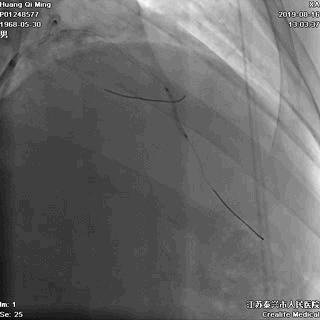

LAD PCI过程

8atm,2.0*10 切割球囊对斑块进行切割

16atm,NC球囊对斑块进行预处理

2.0*25 药物洗脱球囊,8atm*60秒释放药物

2.5*25 药物洗脱球囊,8atm*60秒释放药物

术后即刻效果满意